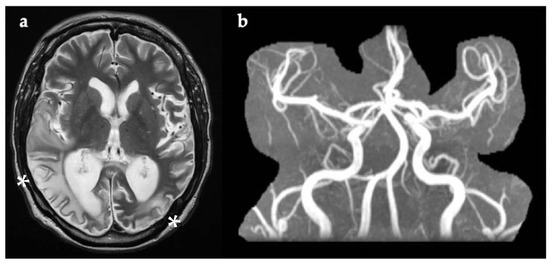

Two weeks later, he re-presented to the ED with acute onset expressive aphasia. There was no associated weakness, visual problems, dysphagia, gait disturbance, or seizure activity, and he was normotensive. ECG was in sinus rhythm. Brain CT showed a new hypodensity involving both the grey and white matter within the left temporal lobe, consistent with a subacute left middle cerebral artery (MCA) infarct. However, CT angiogram did not identify a stenosis or occlusion of the proximal intracranial arteries. The onset of symptoms was unclear, so intravenous thrombolysis was not administered, and he commenced aspirin and clopidogrel in addition to atorvastatin. Echocardiogram confirmed hypertrophic cardiomyopathy. During his admission, he suffered several generalised tonic–clonic seizures and recurrent strokes also involving the occipital lobe, despite the antiplatelet therapy. Interictal EEG did not show epileptic activity, but there was an excess of slow activity over the left hemisphere, in keeping with focal cerebral dysfunction at this site.

Brain MRI (Figure 3) undertaken 24 h after symptom onset confirmed an acute/subacute lesion in the left temporal lobe, which exhibited restricted diffusion on DWI. A follow up brain MRI performed after seven days showed extension of the lesion into the left occipital lobe (Figure 3), compatible with a mitochondrial stroke-like lesion. Levetiracetam was initiated and antiplatelets were discontinued. After starting antiepileptic treatment, seizures stopped and no further SLEs were observed. Since discharge, he has been well and his expressive aphasia has improved.

Figure 3. Axial brain MRI 24 h (a,b) and seven days (c) after symptom onset. Evidence of restricted diffusion in left temporal lobe (DWI) (a, white arrow). T2-FLAIR showing cortical and gyral swelling in left temporal lobe (b, white arrow). Image (c, white arrow) was taken seven days after symptom onset and shows extension of lesion on the left occipital lobe. Abbreviations: DWI, diffusion-weighted imaging; FLAIR, fluid attenuated inversion recovery imaging.